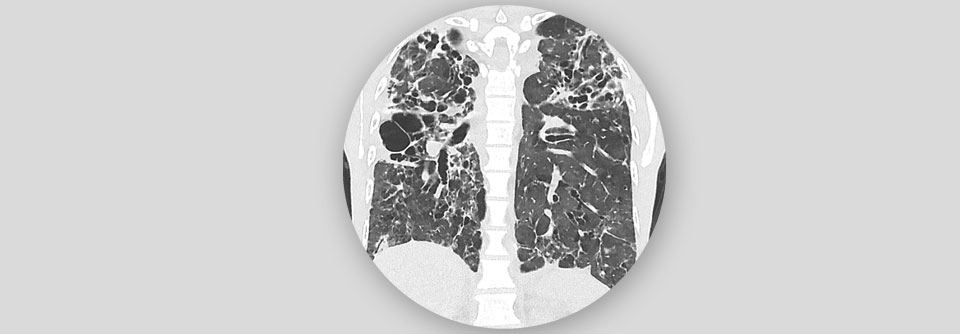

Die ILD geht mit einer Entzündung bzw. Vermehrung von Bindegewebsfasern im Bereich des Lungengerüstes einher und kann in einer Fibrose münden. Die ILD geht mit einer Entzündung bzw. Vermehrung von Bindegewebsfasern im Bereich des Lungengerüstes einher und kann in einer Fibrose münden. © Science Photo Library/Fung, K.H.

Checkpoint-Inhibitoren können interstitielle Lungenerkrankungen (ILD) induzieren. Diese sind bekanntermaßen lebensbedrohlich. Studien zufolge weisen Patienten mit nicht-kleinzelligem Bronchialkarzinom (NSCLC) ein erhöhtes Risiko für eine manifeste ILD auf, wenn sie bereits zuvor interstitielle Auffälligkeiten in der Lunge haben. Japanische Wissenschaftler untersuchten inwiefern diese vorhandenen Vorstufen die Gefahr einer ILD in Menschen mit anderen Krebsarten erhöhen.